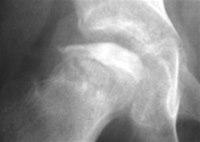

Det vil bli tatt blodprøver av barnet. En røntgenundersøkelse er også nødvendig. De første ukene etter at sykdommen oppstod, kan røntgenbildene være normale. Men etter noen uker vil røntgen kunne vise forandringer i lårbeinshodet. Tidlig i sykdomsforløpet kan derfor andre undersøkelser som ultralyd eller MR, være aktuelle.